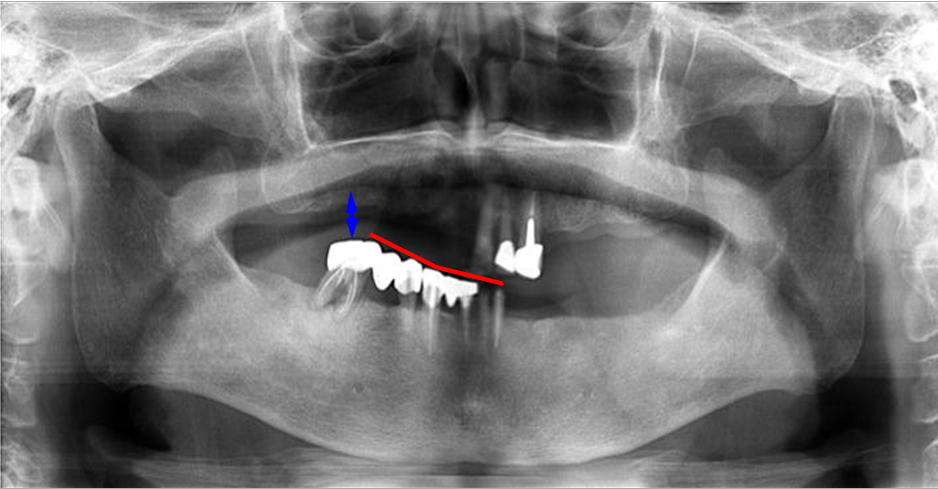

上の2枚のレントゲンは上下奥歯の咬合関係が無く左右前後の咬合崩壊が起きています。

この患者様は、〇 の歯以外は全て抜歯せざるを得ない状態でした。

歯がない箇所の放置は、咬合崩壊を必ず起こします。

義歯が使えないとの主訴で来院されました。左右、前後、歯の高さは完全に崩壊。

この噛み合わせで義歯を作ったところで、噛み合わせはズレ、義歯を入れるスペースも不足(↕)しています。

義歯を新製はしたが「噛み辛い」「ガタつく」「痛い」は、咬合関係の崩壊を修正せず、基準を無視し新製してしまった症状と大いに考えられます。

しかし『咬合崩壊』の治療は困難であり、治療期間は長期に渡ります。

『咬合崩壊』は、ご自身に大いに責任があり、知らなかったでは済まされないのです。 |